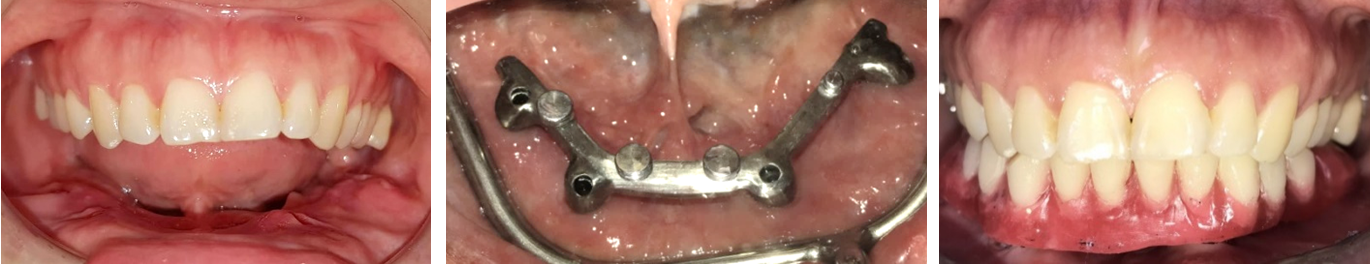

Tại Bệnh viện Răng Hàm Mặt TP.HCM, chúng tôi đã thực hiện thành công ca lâm sàng trên một bệnh nhân nữ (38 tuổi). Chị đã trải qua vài lần phẫu thuật điều trị u men xương hàm dưới và sau cùng là cắt đoạn xương hàm dưới từ góc hàm phải sang trái. Để giúp bệnh nhân phục hồi chức năng ăn nhai cũng như thẩm mỹ khuôn mặt, chúng tôi đã tiến hành phẫu thuật ghép xương mác vi phẫu, cấy ghép implant và hoàn tất với phục hình toàn hàm trên 04 implant.

Thử răng

Phục hình sau cùng

Sau điều trị